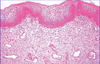

Describe the structure of the uterine tubes?

Serosa: mesothelium plus thin connective tissue

Muscularis: smooth muscle

Mucosa: connective tissue plus epithelium